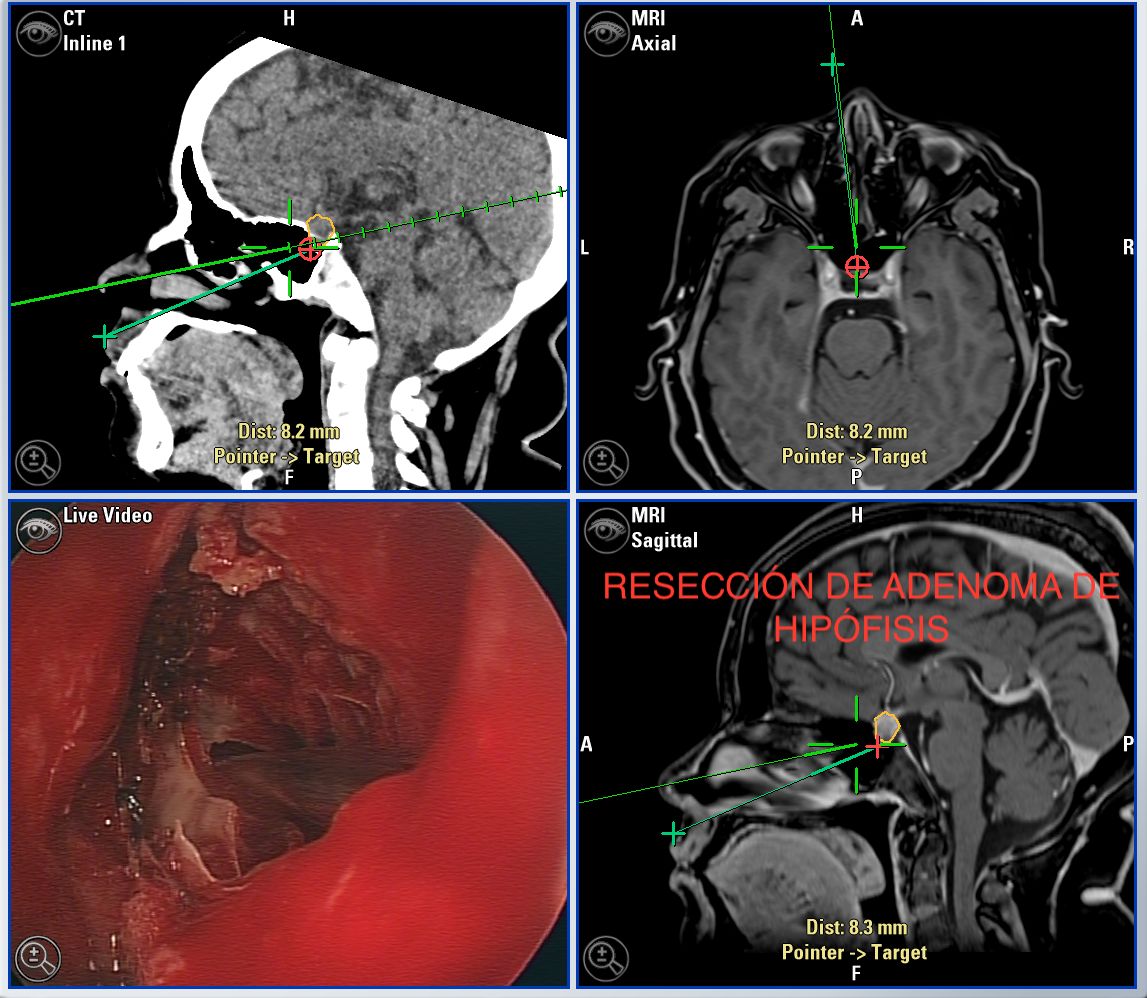

Microcirugía de la hipófisis y región selar